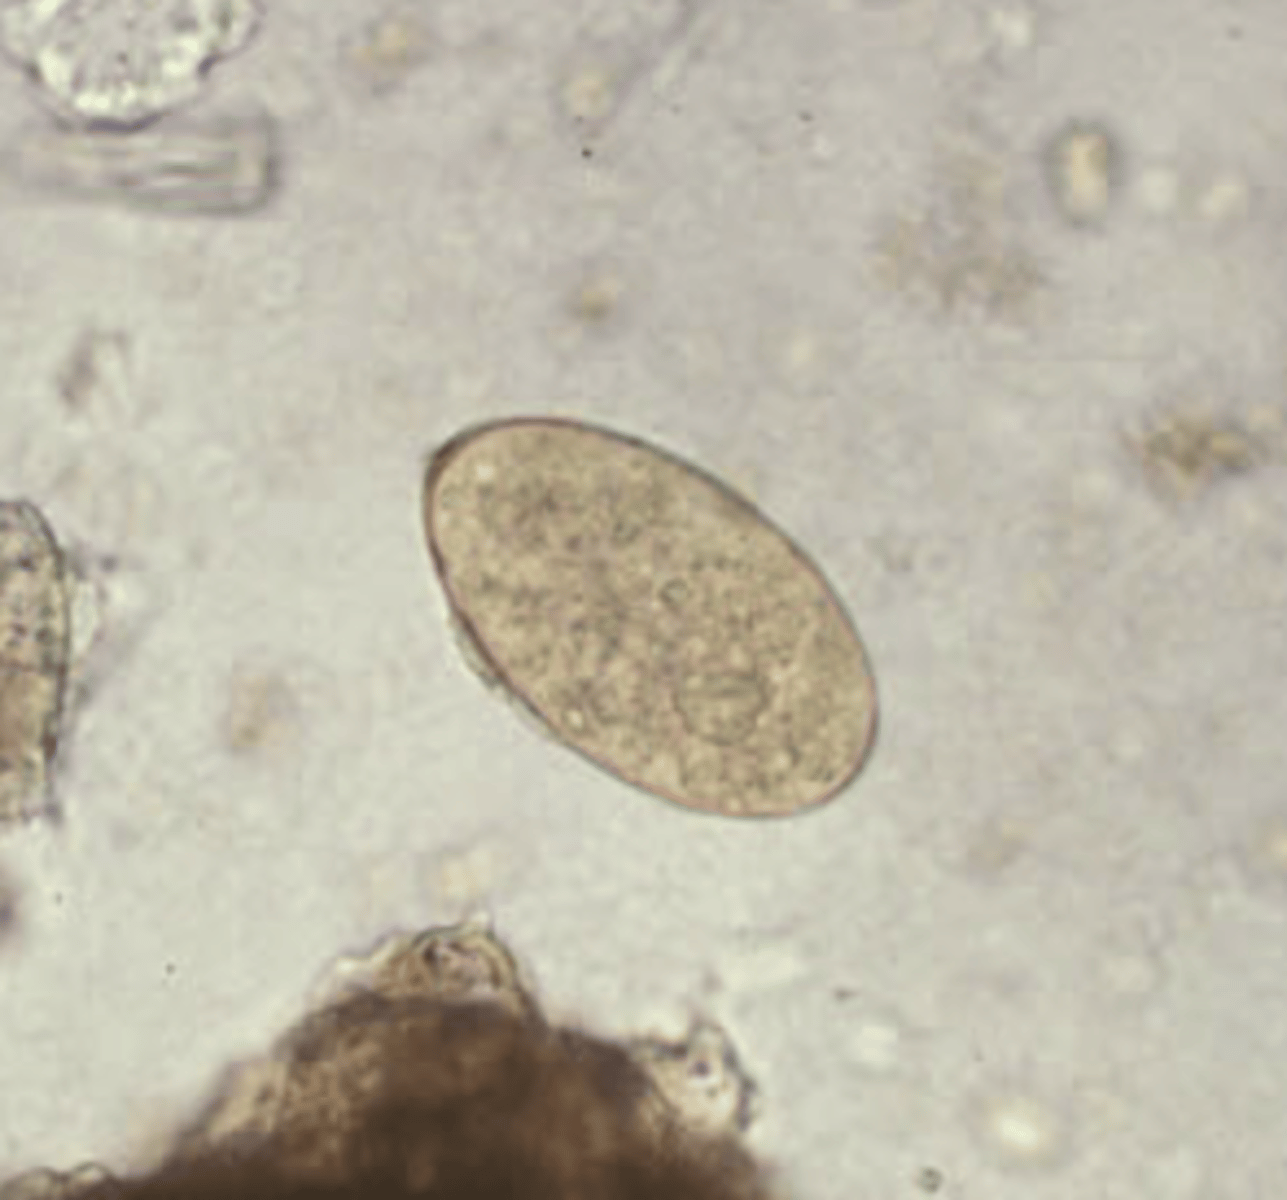

Clonorchis sinensis